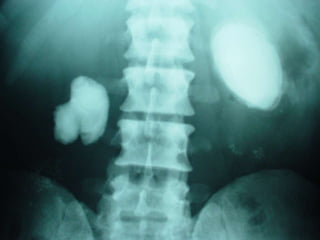

Investigations

i.v.u

To detect the presence of stone